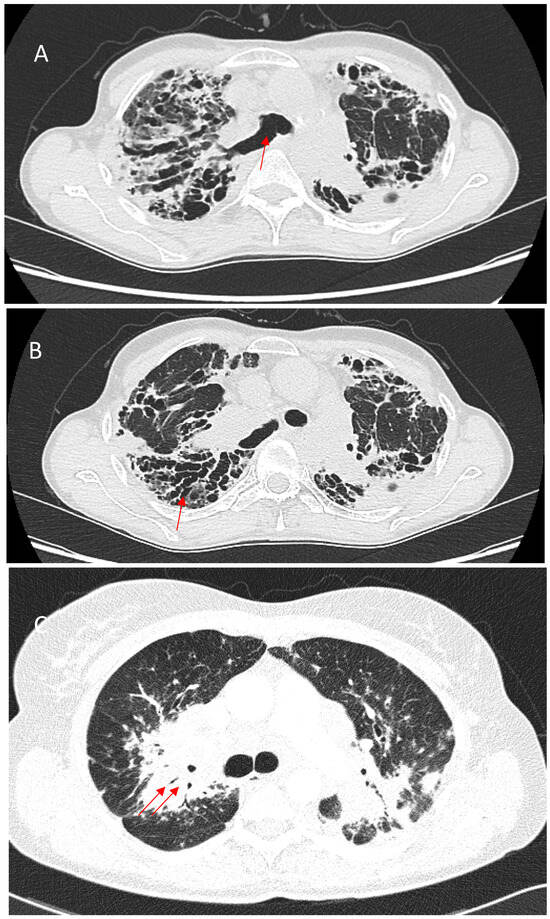

5.1.2. Bronchial Distortion

9.3. Acute Exacerbations